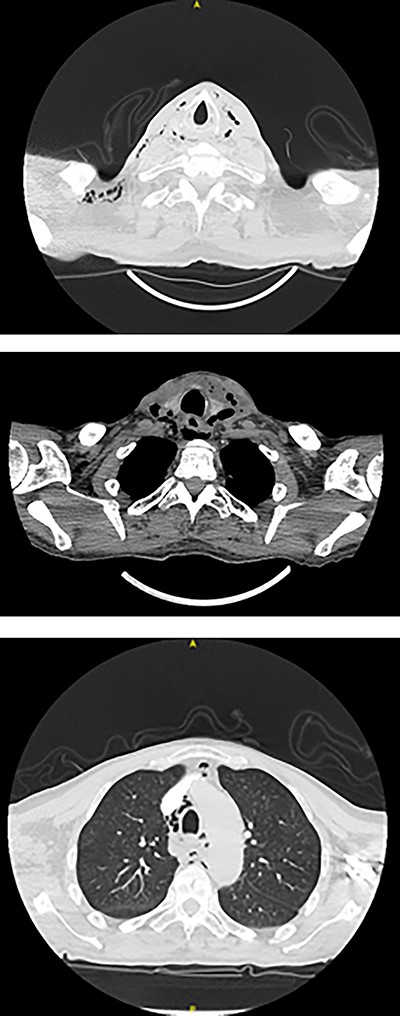

Subsequent pan-endoscopy and neck exploration confirmed multiple slit-like four or five mucosal perforations in left posterior pharyngeal wall and left piriform fossa with muco-purulent discharge (Fig. 4). Two corrugated drains, one directed inferiorly towards pharynx and one superiorly, were secured. Histology of tissue biopsy confirmed acute and chronic inflammation with granulation, which was negative for dysplasia, malignancy and cytomegalovirus, fungal, acid-fast bacilli infections. No microbial growth was obtained from culture.

Pharyngoscopy showing slit-like mucosal perforations in left posterior pharyngeal wall and left piriform fossa with muco-purulent discharge.

He was managed conservatively. Two days post-operatively, surgical emphysema had resolved and there was minimal drain output. Contrast swallow 6 days post-operatively showed aspiration and repeat pharyngoscopy, 10 days post-operatively, showed healing perforations (Fig. 5).